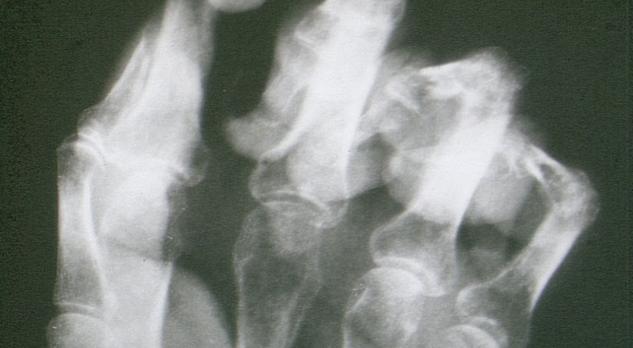

Multidisciplinaire richtlijn complex regionaal pijnsyndroom Lees meer over Multidisciplinaire richtlijn complex regionaal pijnsyndroom Multidisciplinaire richtlijn complex regionaal pijnsyndroom

In dit artikel wordt aandacht geschonken aan de multidisciplinaire richtlijn Complex regionaal pijnsyndroom type I (CRPS-I). Aan de orde komen epidemiologie, pathofysiologie, predisponerende factoren, natuurlijk beloop en de belangrijkste conclusies en aanbevelingen ten aanzien van diagnostiek en therapie. Wat uitgebreider wordt stilgestaan bij het vaststellen van de belastbaarheid en begeleidingsadviezen zoals in de richtlijn in een apart hoofdstuk verwoord. Hoewel klinisch zeer relevant, komen de vele onderzoeken naar het nut van (aanvullende) diagnostiek en behandeling minder uitgebreid aan bod.